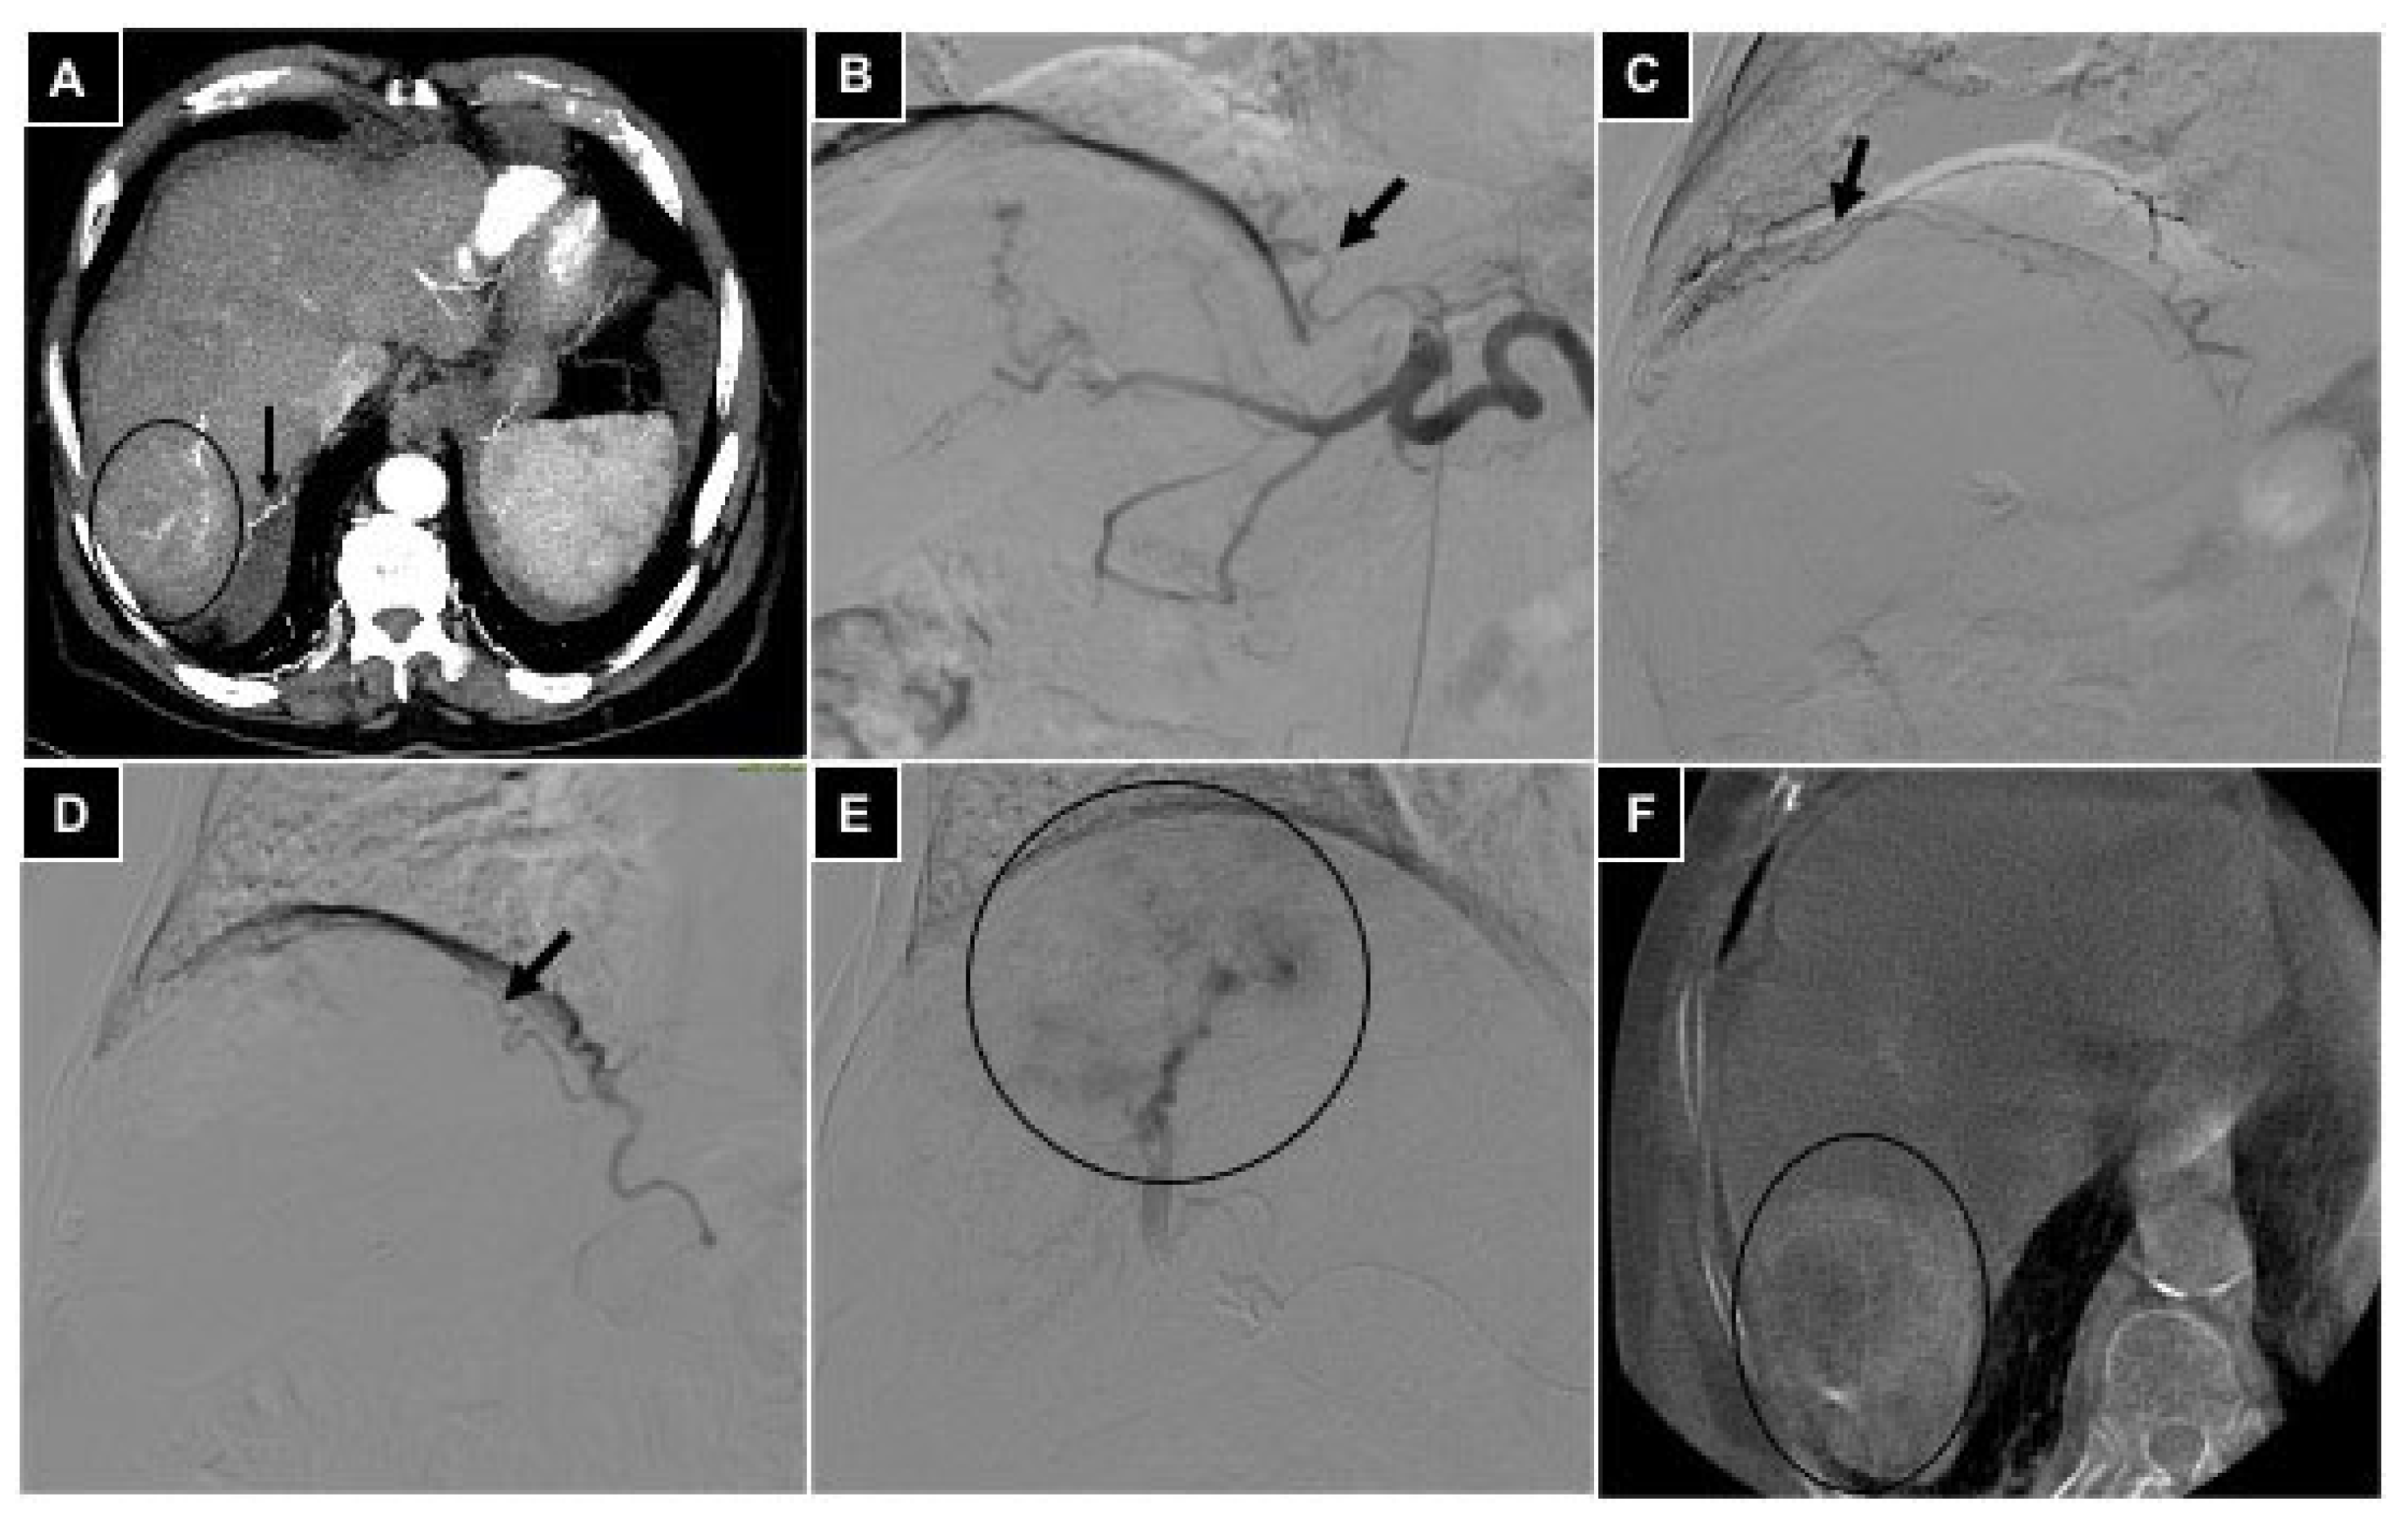

| 2 TAE | Gastric cancer | 2 Left hepatic a. | Left gastric a. | Bland microparticles |